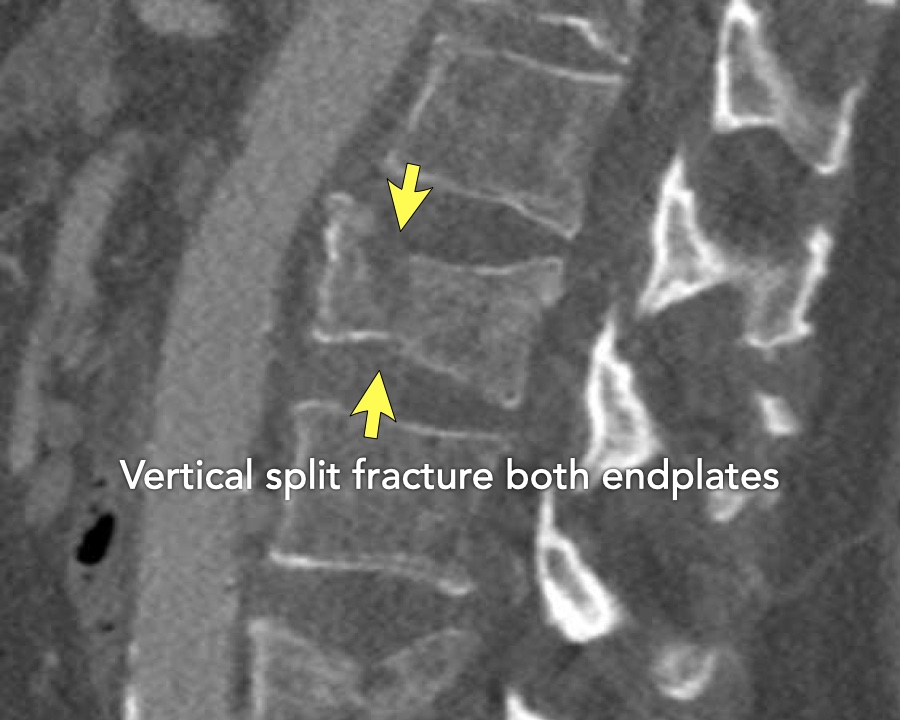

A2 Split fracture

A2 is a fracture of both endplates without involvement of the posterior wall of the vertebral body.

What is the highest AO-type of injury?

Findings:

- No C or B injury

- Fracture of the vertebral body with involvement of both endplates (1+1 points), no posterior wall involvement

Conclusion

injury type A2